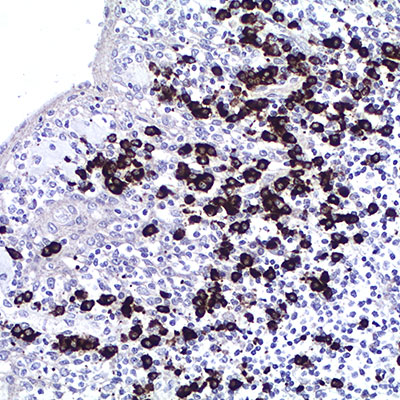

Lambda Light Chain

Este kit está diseñado para el estudio de monoclonalidad de cadenas ligeras Lambda en los tumores linfoides, mieloides y en otros Síndromes Linfoproliferativos, sobre secciones de tejidos fijados en formalina tamponada e incluidos en parafina.